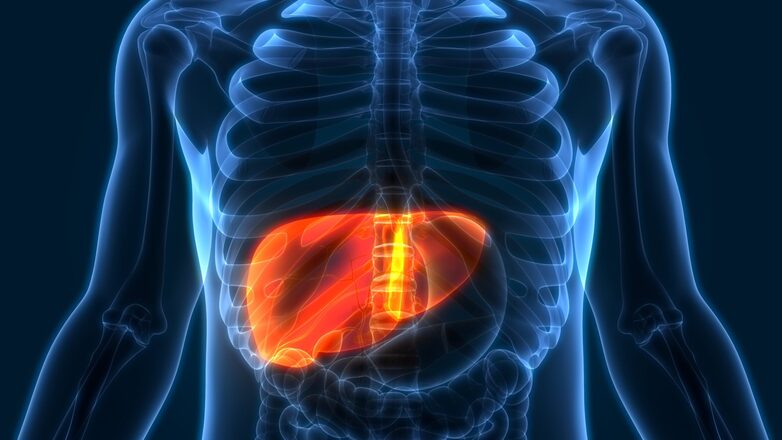

Η νόσος Wilson χαρακτηρίζεται από την παθολογική συσσώρευση του χαλκού σε διάφορα όργανα και ιστούς του σώματος. Προκαλείται από μεταλλάξεις στο γονίδιο ATP7B, το οποίο είναι υπεύθυνο για την παραγωγή της πρωτεΐνης μεταφοράς χαλκού, διαταράσσοντας έτσι την απομάκρυνση του χαλκού από τον οργανισμό και οδηγώντας σε του συσσώρευση σε ζωτικά όργανα όπως το ήπαρ και ο εγκέφαλος.

Η θεραπεία της νόσου Wilson είναι απαραίτητη για όλους τους διαγνωσθέντες ασθενείς και απαιτεί δια βίου παρέμβαση. Στόχος της θεραπείας είναι η απομάκρυνση της περίσσειας χαλκού από το σώμα. Οι κύριες θεραπευτικές προσεγγίσεις περιλαμβάνουν τη χρήση χηλικών παραγόντων, όπως η πενικιλλαμίνη και η τριεντίνη, οι οποίες δεσμεύουν τον χαλκό και διευκολύνουν την αποβολή του μέσω των ούρων. Σε μερικές περιπτώσεις, μπορεί να χορηγηθούν άλατα ψευδαργύρου που περιορίζουν την απορρόφηση του χαλκού στο έντερο. Συνιστάται επίσης μια δίαιτα χαμηλή σε χαλκό, η οποία περιλαμβάνει την αποφυγή τροφών όπως το συκώτι, τα οστρακοειδή, οι ξηροί καρποί, η σοκολάτα και τα μανιτάρια. Στα προχωρημένα στάδια της νόσου, όπου παρατηρείται κίρρωση και ηπατική ανεπάρκεια, η μεταμόσχευση ήπατος αποτελεί την μοναδική διαθέσιμη θεραπευτική επιλογή.